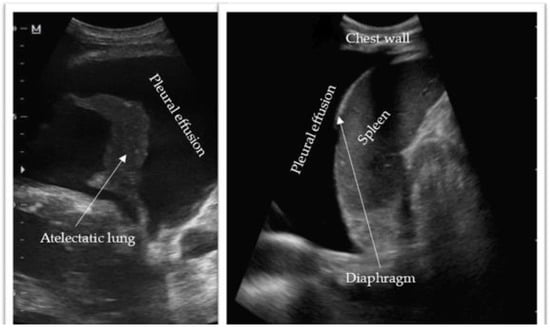

Thoracic ultrasonography has emerged as an invaluable diagnostic tool for assessing pleural effusions. Offering portability, noninvasiveness, and radiation-free imaging, it facilitates convenient and safe bedside evaluation (Figure 3). The accuracy of thoracic ultrasonography in detecting pleural effusions has been confirmed through numerous studies [8,9,10]. Notably, a 2011 study by Xirouchaki et al. reported 100% sensitivity, specificity, and diagnostic accuracy for thoracic ultrasound in pleural effusion diagnosis [9]. The International Consensus Conference on Lung Ultrasound supports this, asserting that “for effusion detection, lung ultrasound is more accurate than supine radiography and equally accurate to CT” [7,11]. Thoracic ultrasonography facilitates the assessment of fluid homogeneity, septation, and echogenicity. Several studies highlight ultrasound’s superiority over CT imaging in detecting intrinsic pleural effusion characteristics. Depending on the effusion’s etiology and complexity, four main sonographic patterns can be identified: anechoic (purely black), complex non-septated (black with white strands), complex septated (black with white septa), and homogenously echogenic (purely white) (Table 1) [7,12]. Complex appearances are typically associated with exudative effusions, while anechoic effusions can be either transudative or exudative. Echogenic effusions require drainage to explore for underlying etiology, such as empyema or hemothorax. Patient positioning significantly influences thoracic ultrasound evaluation [12]. Pleural fluid accumulates dependently within the thorax, making the seated upright position ideal as it encourages fluid movement to the lower thorax. In cases where patients face challenges or contraindications to upright positioning, such as mechanically ventilated critically ill patients, the supine position with the ipsilateral arm adducted across the chest toward the contralateral side is preferred [13]. Accurately identifying the diaphragm’s position relative to the pleural effusion is crucial to avoid diaphragmatic injury during drainage. Further discussion on the procedural role of thoracic ultrasonography will be provided in the subsequent sections.

Figure 3. Thoracic ultrasonography demonstrating an anechoic pleural effusion with surrounding structures. Image (left) courtesy of Mohammad Osama Hussein Yonso, Radiopaedia.org, rID: 22793. Image (right) courtesy of Zhan Lim, Radiopaedia.org, rID: 94919.